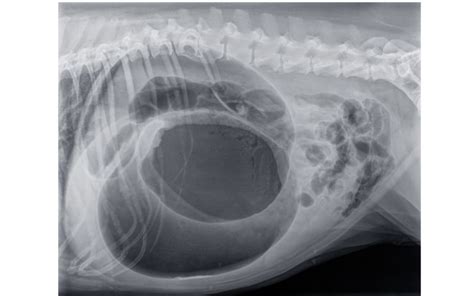

Cudzie predmety v tráviacom trakte

Častrokrát sa stáva, že pri veľkej obľube hračiek sa niekedy dostane do tráviaceho traktu celá hračka alebo jej časť, prípadne iný cudzí predmet (kamene, gaštany, ponožky, spodné prádlo...). Ak má Váš pes sklony k trhaniu, noseniu a obhrýzaniu takýchto predmetov, je lepšie tieto predmety odstrániť z jeho dosahu, prípadne sa zamerať na kvalitu hračiek.

Niekedy majiteľ spozoruje prehltnutie predmetu, niekedy ho na situáciu upozorní chýbanie predmetu alebo až prvé príznaky zdravotných problémov jeho psa. V každom prípade treba kontaktovať veterinárneho lekára, aby sa lokalizoval cudzí predmet a zvolil najlepší postup na riešenie. Prvé príznaky, ktoré môžete spozorovať, sú nechutenstvo, napínanie na vracanie, vracanie, apatia.

Ako postupovať v riešení závisí od lokalizácie predmetu - pažerák, žalúdok, tenké črevo..., od typu a tvaru predmetu a celkového zdravotného stavu zvieraťa. Najčastejší spôsob je operácia, kde sa príslušný predmet vyberie, skontroluje sa tkanivo, kde bol útlak cudzím predmetom, prípadne sa urobí revízia. Endoskopia sa odporúča len v špecifických prípadoch, väčšinou hrozí poškodenie pažeráku pri spätnom pohybe predmetu.